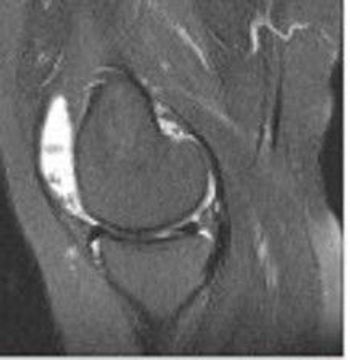

For a woman of her age and medical history with a weight problem, early osteoarthritis might not be an unreasonable diagnosis for knee pain and swelling after treadmill walking. But in rheumatology, things are so often not what they seem at first glance. What is your diagnosis?